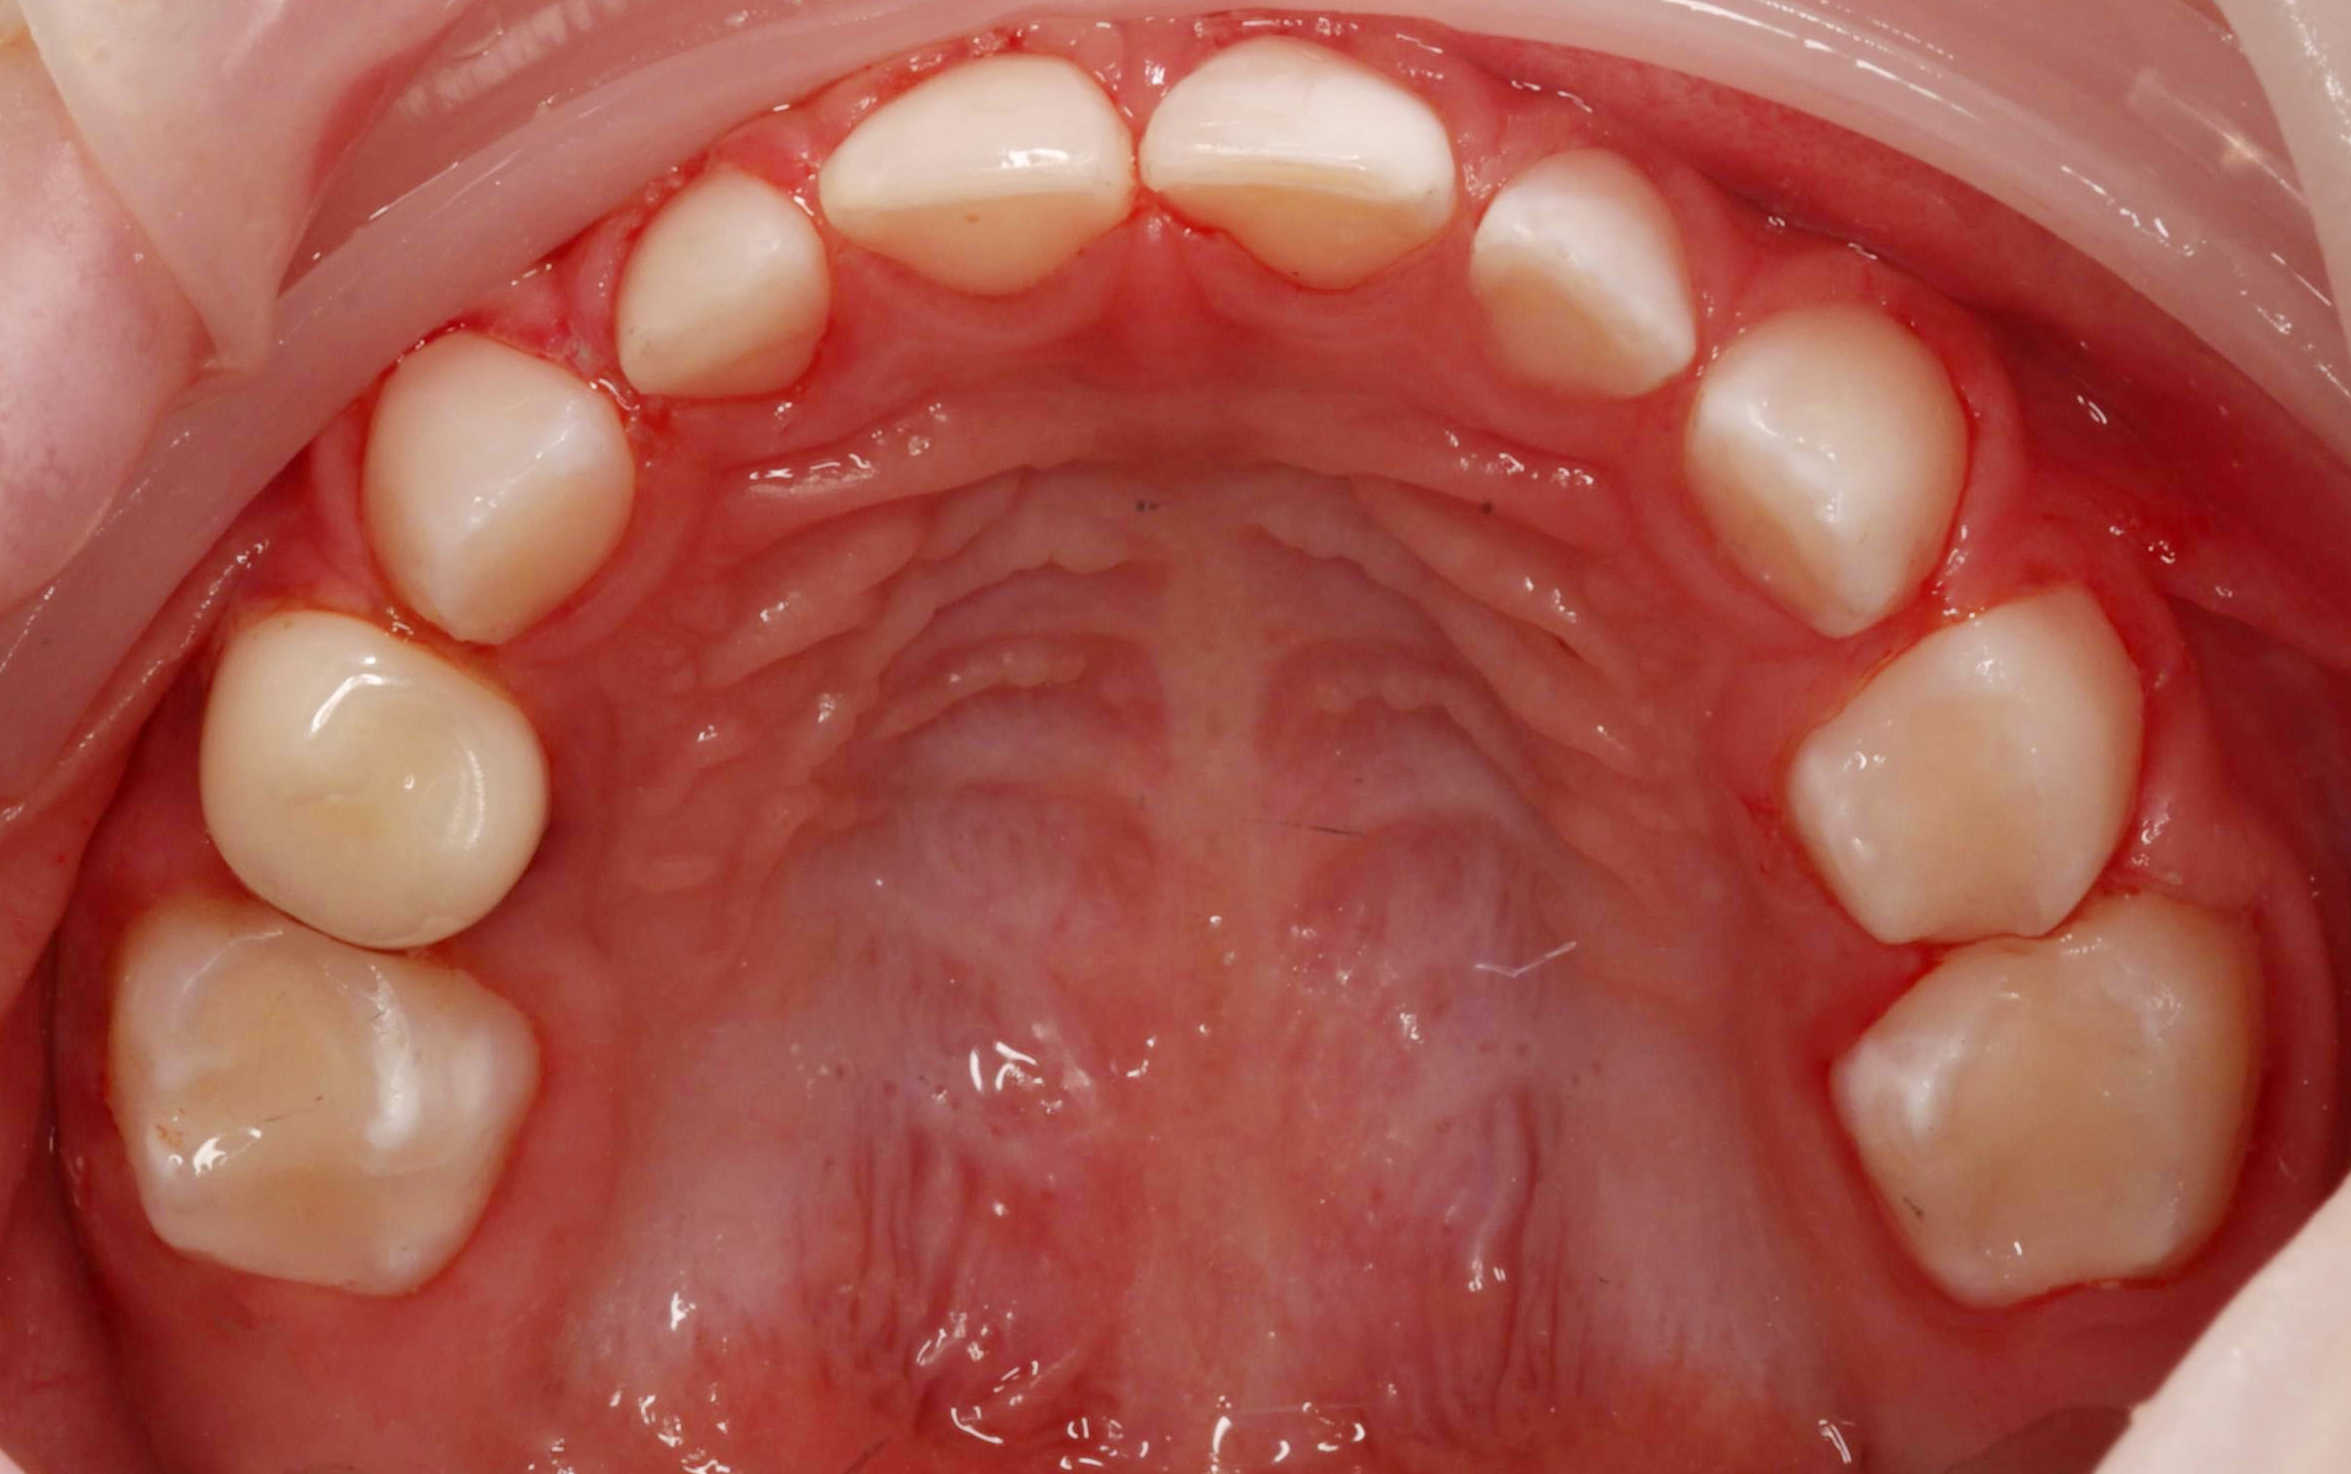

Бұрын

Бұрын

Бұрын

Бұрын